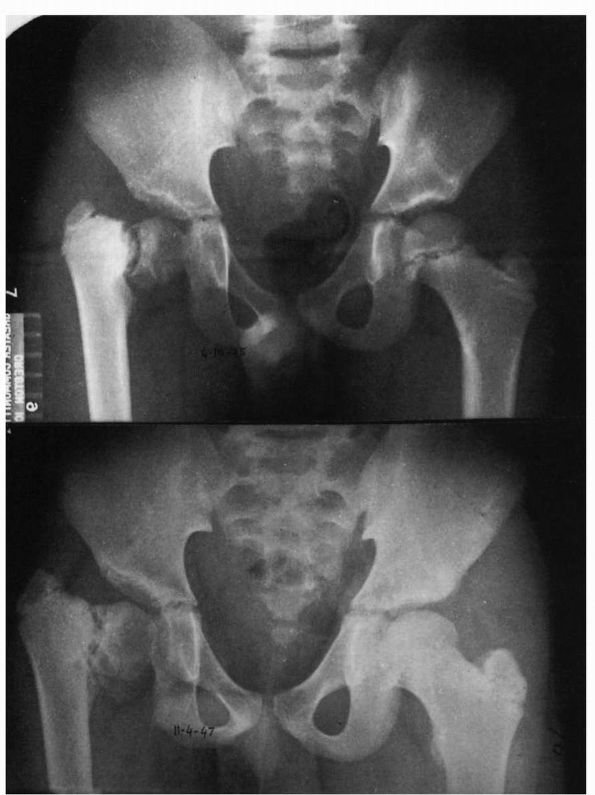

promote ossification of the defect and to correct the varus deformity,

allowing restoration of the mechanical advantage of the hip abductors

to improve gait and to equalize limb lengths. In progressive coxa vara,

the natural history suggests increasing deformity (Figure 15-28),

decreasing function, and early degenerative joint disease. The general

indications for surgical treatment include increasing coxa vara and a

neck-shaft angle of less than 100°. In mild, nonprogressive cases with

a neck-shaft angle of greater than 100° and a Hilgenreiner epiphyseal

angle of less than 45°, resolution of the defect may occur, and

observation of the patient with serial follow-up radiographs is

indicated. In patients with a limp, progressive deformity, and a

Hilgenreiner epiphyseal angle of greater than 60°, intertrochanteric or

subtrochanteric abduction osteotomy is the treatment of choice (Figure 15-29).

In these patients, the neck-shaft angle should be restored to decrease

the shear stress across the vertical defect. With surgery, the defect

generally heals, but growth plate arrest may be seen in a significant

number of patients, leading to limb length inequality. Generally,

patients older than 5 years of age at the time of surgery maintain

their correction.

![]() |

|

FIGURE 15-28. Coxa vara development. Note triangular fragment and worsening of condition over a 2-year period (bottom).